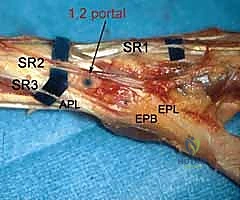

5. The 1-2 Portal

- Location: This portal lies between the first and second dorsal extensor compartments.

- Anatomy:

- First Compartment: Contains the abductor pollicis longus (APL) and extensor pollicis brevis (EPB) tendons.

- Second Compartment: Contains the extensor carpi radialis longus (ECRL) and extensor carpi radialis brevis (ECRB) tendons.

- Neurovascular Risks: The superficial radial nerve (SRN) is highly vulnerable in this region. Its branches can be quite variable. Meticulous blunt dissection and careful palpation of the tendons are crucial.

- Function: Used less frequently than 3-4 or 4-5, but provides an excellent view for radial styloidectomy, visualizing the radioscaphoid joint, and addressing specific pathologies on the radial side.